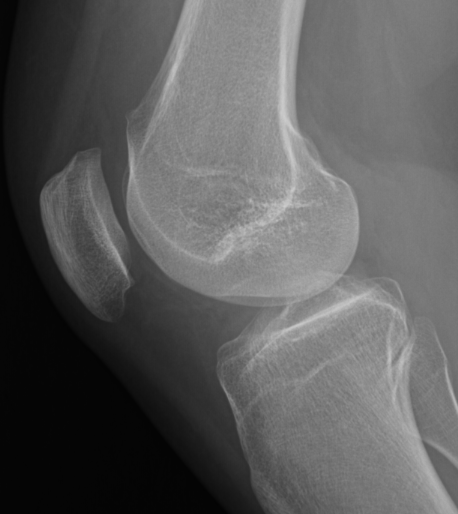

Trochlea dysplasia / Sulcus angle

- normal < 140o

- > 140o flattened

Normal trochlea / sulcus

Trochlea dysplasia